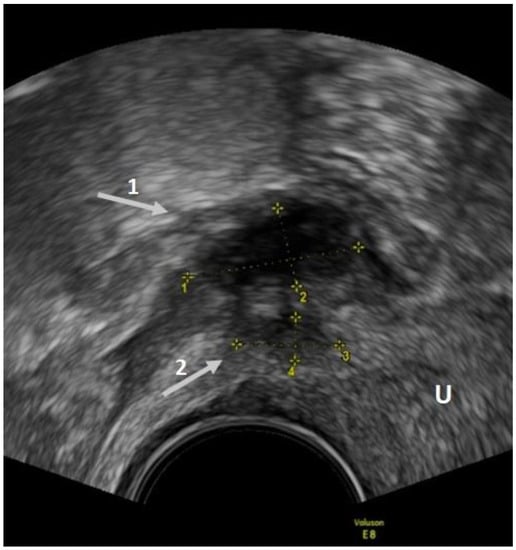

2. Transvaginal Ultrasound

2.1. Ovarian Endometriosis

- Collins, B.G.; Ankola, A.; Gola, S.; McGillen, K.L. Transvaginal US of Endometriosis: Looking Beyond the Endometrioma with a Dedicated Protocol. RadioGraphics 2019, 39, 1549–1568. [Google Scholar] [CrossRef]

- Van Holsbeke, C.; Van Calster, B.; Guerriero, S. Endometriomas: Their ultrasound characteristics. Ultrasound Obstet. Gynecol. 2010, 35, 730–740. [Google Scholar] [CrossRef]

- Guerriero, S.; Condous, G.; van den Bosch, T.; Valentin, L.; Leone, F.P.G.; Van Schoubroeck, D.; Exacoustos, C.; Installé, A.J.F.; Martins, W.P.; Abrao, M.S.; et al. Systematic approach to sonographic evaluation of the pelvis in women with suspected endometriosis, including terms, definitions and measurements: A consensus opinion from the International Deep Endometriosis Analysis (IDEA) group. Ultrasound Obstet. Gynecol. 2016, 48, 318–332. [Google Scholar] [CrossRef] [PubMed]